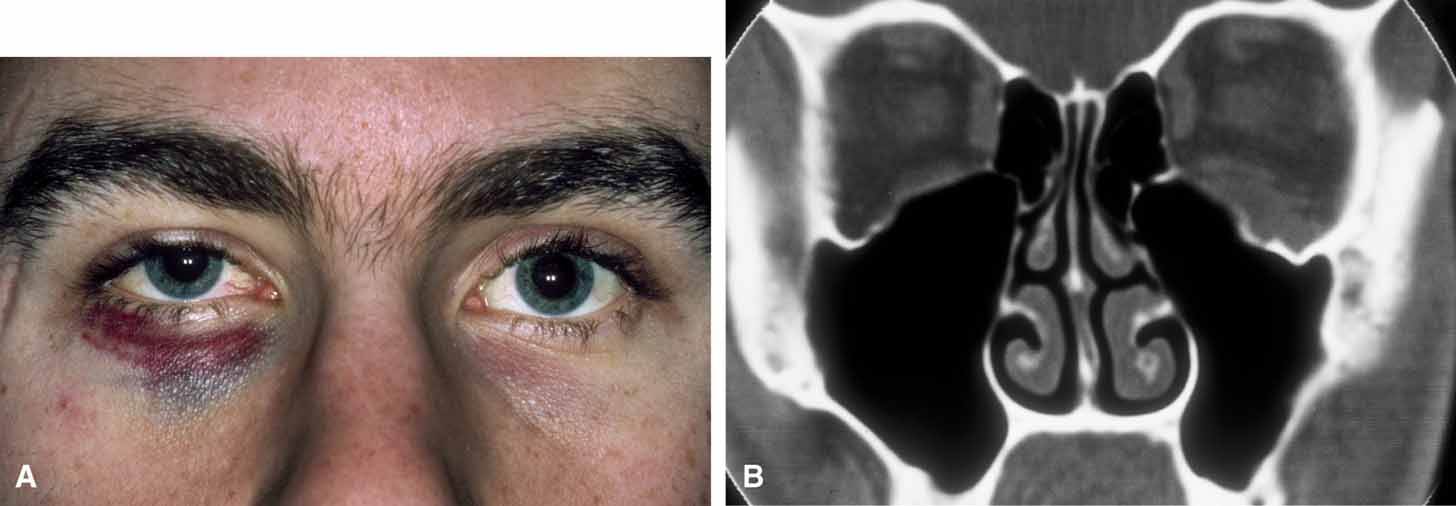

Mucoceles of the frontal and ethmoid sinuses are most common; and their clinical features are usually related to a mass effect and inflammation.33–34 The enlargement of the mucocele may be insidious, with proptosis and displacement of the globe being manifest in association with a palpable, smooth-walled mass in the upper inner quadrant of the orbit (Fig. 8).

Fig. 8 Frontal sinus mucocele in a man with a history of sinus disease. A. The left eye is displaced inferotemporally, indicating the superior medial location. B. Coronal section of a computed tomogram shows expansion of the opacified left frontal sinus with loss of the bony anterior and inferior walls of the frontal sinus.